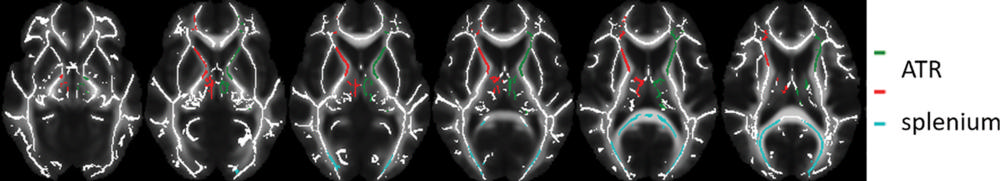

Figure 2. Images of regions of interest (colored lines) in the white matter skeleton representation. Data from left and right anterior thalamic radiation (ATR) were averaged.